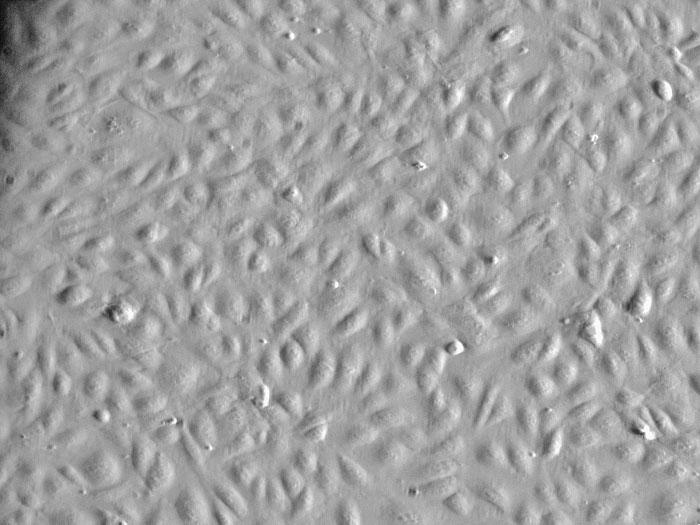

ScienCell社では、HUVEC(ヒト臍帯静脈内皮細胞)を販売しております。

HUVECは、循環器領域における医薬品開発、高分子輸送、血管形成および血管新生の研究などの実験に使用されています。